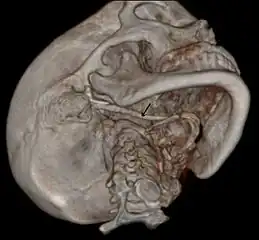

3D-reconstructed CT scan showing bilateral stylohyoid ligament ossification- 3D reconstructed CT scan showing elongated styloid process (right side)

Imaging is important and is diagnostic. Visualizing the styloid process on a CT scan with 3D reconstruction is the suggested imaging technique.[13] The enlarged styloid may be visible on an orthopantogram or a lateral soft tissue X ray of the neck.